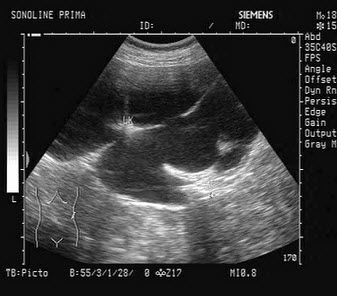

53、单项选择题

某患者25岁,高热,肝区疼痛。肝脏声像图表现如图,结合病史,最可能的诊断是()